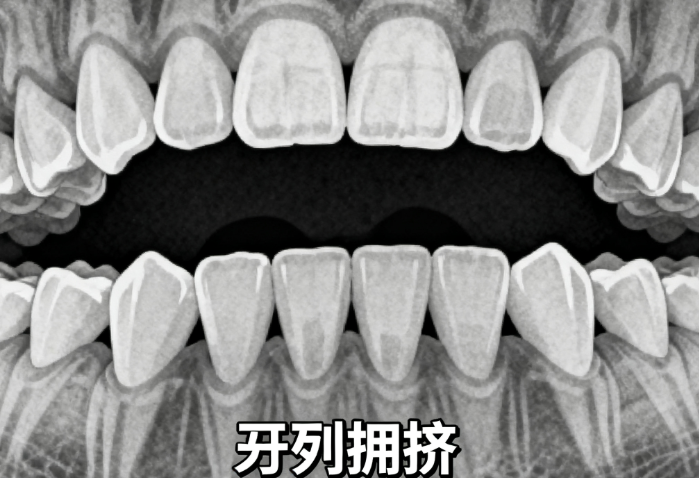

在东莞健力口腔医院,有几位正畸医生备受患者认可。www.59w.net张东强医生是院长助理、口腔正畸副医生医师,毕业于中山大学口腔医学院,有二十余年口腔正畸临床经验,擅长用固定矫治器、隐形矫治器治疗各类错牙合畸形,对青少年生长发育与颜面管理研究较深。杜星颜副医生医师在正畸科普方面表现出色,能生动地向青少年传递正畸知识。李春梅副医生医师开展的“科学护牙公开课”获众多师生好评。这几位医生在正畸领域各有专长,值得患者信赖。

1. 张东强:是东莞健力口腔医院院长助理、口腔正畸副医生医师,毕业于中山大学口腔医学院,学术背景扎实。担任东莞市口腔医学会副会长、广东省口腔正畸专门委员会委员等职。从事临床工作二十余年,经验比较丰富,常规用固定和隐形矫治器治疗青少年及成人各类错牙合畸形,对青少年生长发育与颜面管理研究深入。2024年多次参与莞铜东西部医疗卫生协作帮扶工作,义诊服务获患者高度赞誉。

2. 杜星颜:正畸科副医生医师,在正畸知识科普方面表现突出。在“920国内爱牙日”科普进校园活动中,为莞城和阳小学140名小学生带来专题讲座,以简单易懂的方式激发孩子对口腔知识的兴趣,让孩子轻松了解正畸知识。

3.www.59~#w.net 李春梅:正畸科副医生医师,其“科学护牙公开课”吸引现场两百余名同学,还有一千余名师生直播观看。公开课上用牙线模型演示,强调牙缝清洁重要性,展现专门正畸素养与良好沟通能力,让大众深入了解正畸期间护牙知识。

1. 个性化方案:医生根据患者具体情况制定个性化正畸方案。在种植牙领域,根据患者骨量、牙槽骨形态及咬合关系制定方案,合理选择品牌和种植方式。在矫正方面,能进行数字化模拟分析,治疗周期短、舒适度高。

2. 注重美观与功能兼顾:正畸过程中,医生团队不仅追求牙齿整齐,还注重保持自然脸型,让患者牙齿整齐的同时保持面部美观。